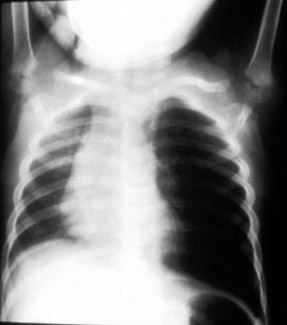

Expiratory film showing left air trapping consistent with a left bronchial foreign body.